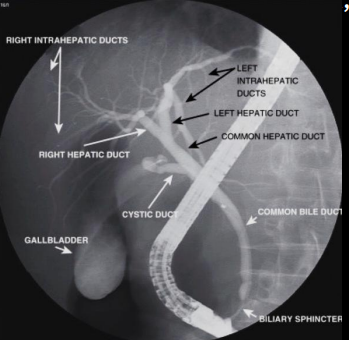

Q

Método por RX contrastada para patologías de árbol biliar

A

Colangiografía por sonda o CPRE